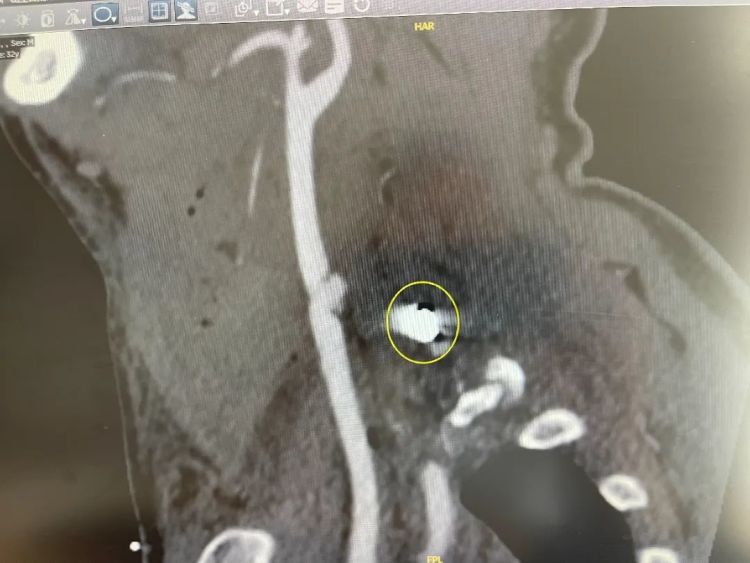

在DSA(数字减影血管造影)检查下,一颗直径约8毫米的异物在影像中显露高密度白色身形,刚好卡在颈椎间隙,没有伤到颈椎 。医生们松了一口气,这也意味着,一切都在他们的掌握中。

卡在颈椎间隙的异物